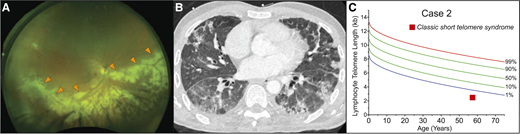

A previously healthy 57-year-old man presented to his physician for evaluation of unilateral vision loss. His family history was positive for acute leukemia in two siblings. His dilated fundus examination showed opacified lesions tracking centrifugally with the retinal vessels in the right eye with areas of necrosis and hemorrhage (Figure 3A). This was suspicious for cytomegalovirus (CMV) retinitis, and laboratory evaluation demonstrated lymphopenia with an absolute lymphocyte count of 800 cells/μL, absolute CD4 count of 339/μL (normal for age, 500 to 1400/μL), and macrocytic anemia (hemoglobin, 11 g/dL; mean corpuscular volume, 101 fL) but an otherwise intact complete blood count. The result of the patient’s serum CMV polymerase chain reaction assay was positive at 79 000 IU/mL. The result of his HIV antibody test was negative. Treatment of CMV retinitis was initiated with intravitreal foscarnet and systemic ganciclovir. During follow-up care, computed tomography (CT) of the chest, performed for complaints of chronic exertional dyspnea, revealed interstitial lung disease (Figure 3B). These findings prompted an evaluation for a telomere disorder, which demonstrated telomere length below the first age-adjusted percentile (Figure 3C). Genetic evaluation showed no mutations in the known genes. The patient’s hypoxia progressed, and he developed acute-on-chronic respiratory failure. Evaluation identified Pneumocystis jirovecii pneumonia as the cause (Figure 3B). He died 4 months after the diagnosis of his CMV retinitis despite maximum supportive care.

Infectious complications can precede onset of bone marrow failure in the short telomere syndromes. (A) Wide-field fundus photograph of CMV retinitis with intraretinal whitening (orange arrowheads) and necrosis along the retinal vasculature and progressing centrifugally. Image generously provided by Dr. Yonwook Kim of the Boston University Medical Center Department of Ophthalmology. (B) Chest CT image showing pleura-based patchy ground-glass opacities and interlobular septal thickening in a patient who developed P. jirovecii pneumonia in the background of interstitial lung disease and CMV retinitis that was ultimately fatal. (C) Lymphocyte telomere length by flowFISH in a patient with telomere-mediated primary T-cell immunodeficiency manifesting in fatal opportunistic infections.